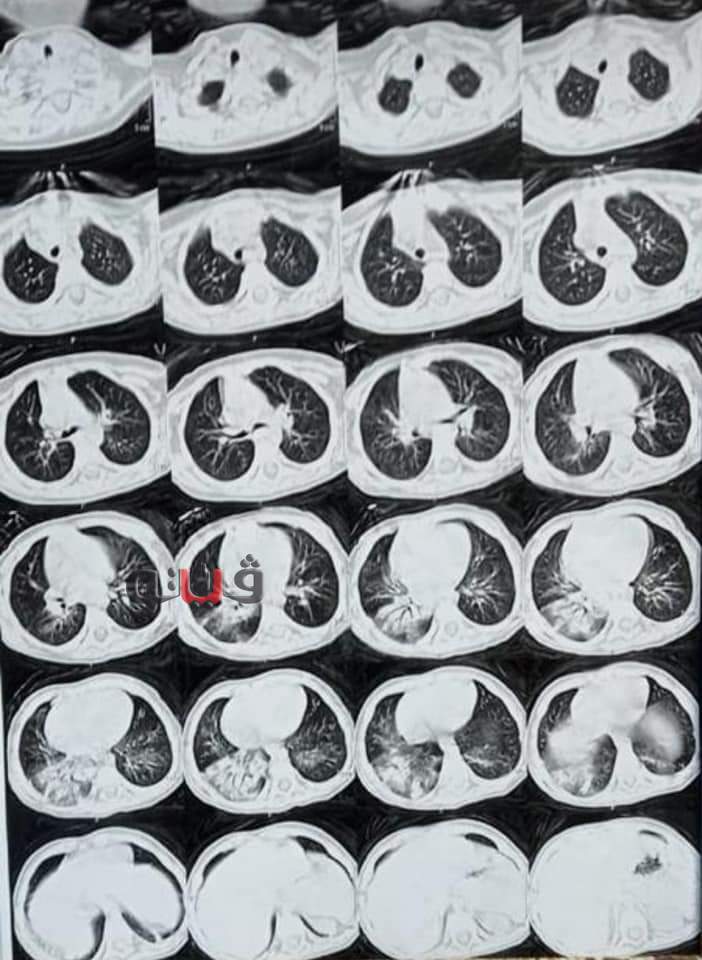

وأشار الجزار إلى ان مستشفى بنها الجامعي استقبل الطفل وعمره عام و٧ شهور وبعد عمل كل الأشعات للطفل كان يرجح أنه يعاني من فيروس كورونا خاصة أن الفيروس أصبح يصيب الأطفال في الوقت الذي يعاني الطفل من صعوبة بالتنفس وانخفاض نسبة الأكسجين.